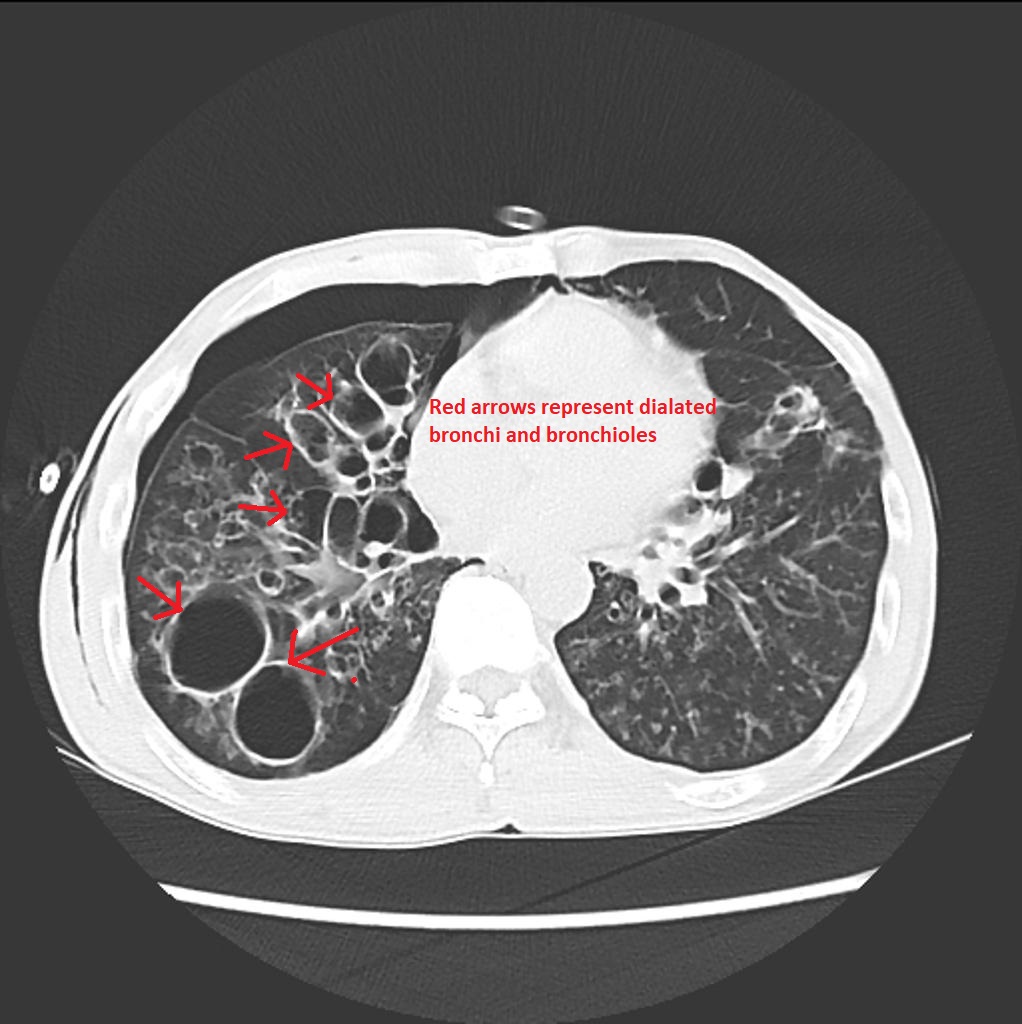

Фиброз Легких Фото Кт

Фиброз Легких Фото Кт 114 фотографий